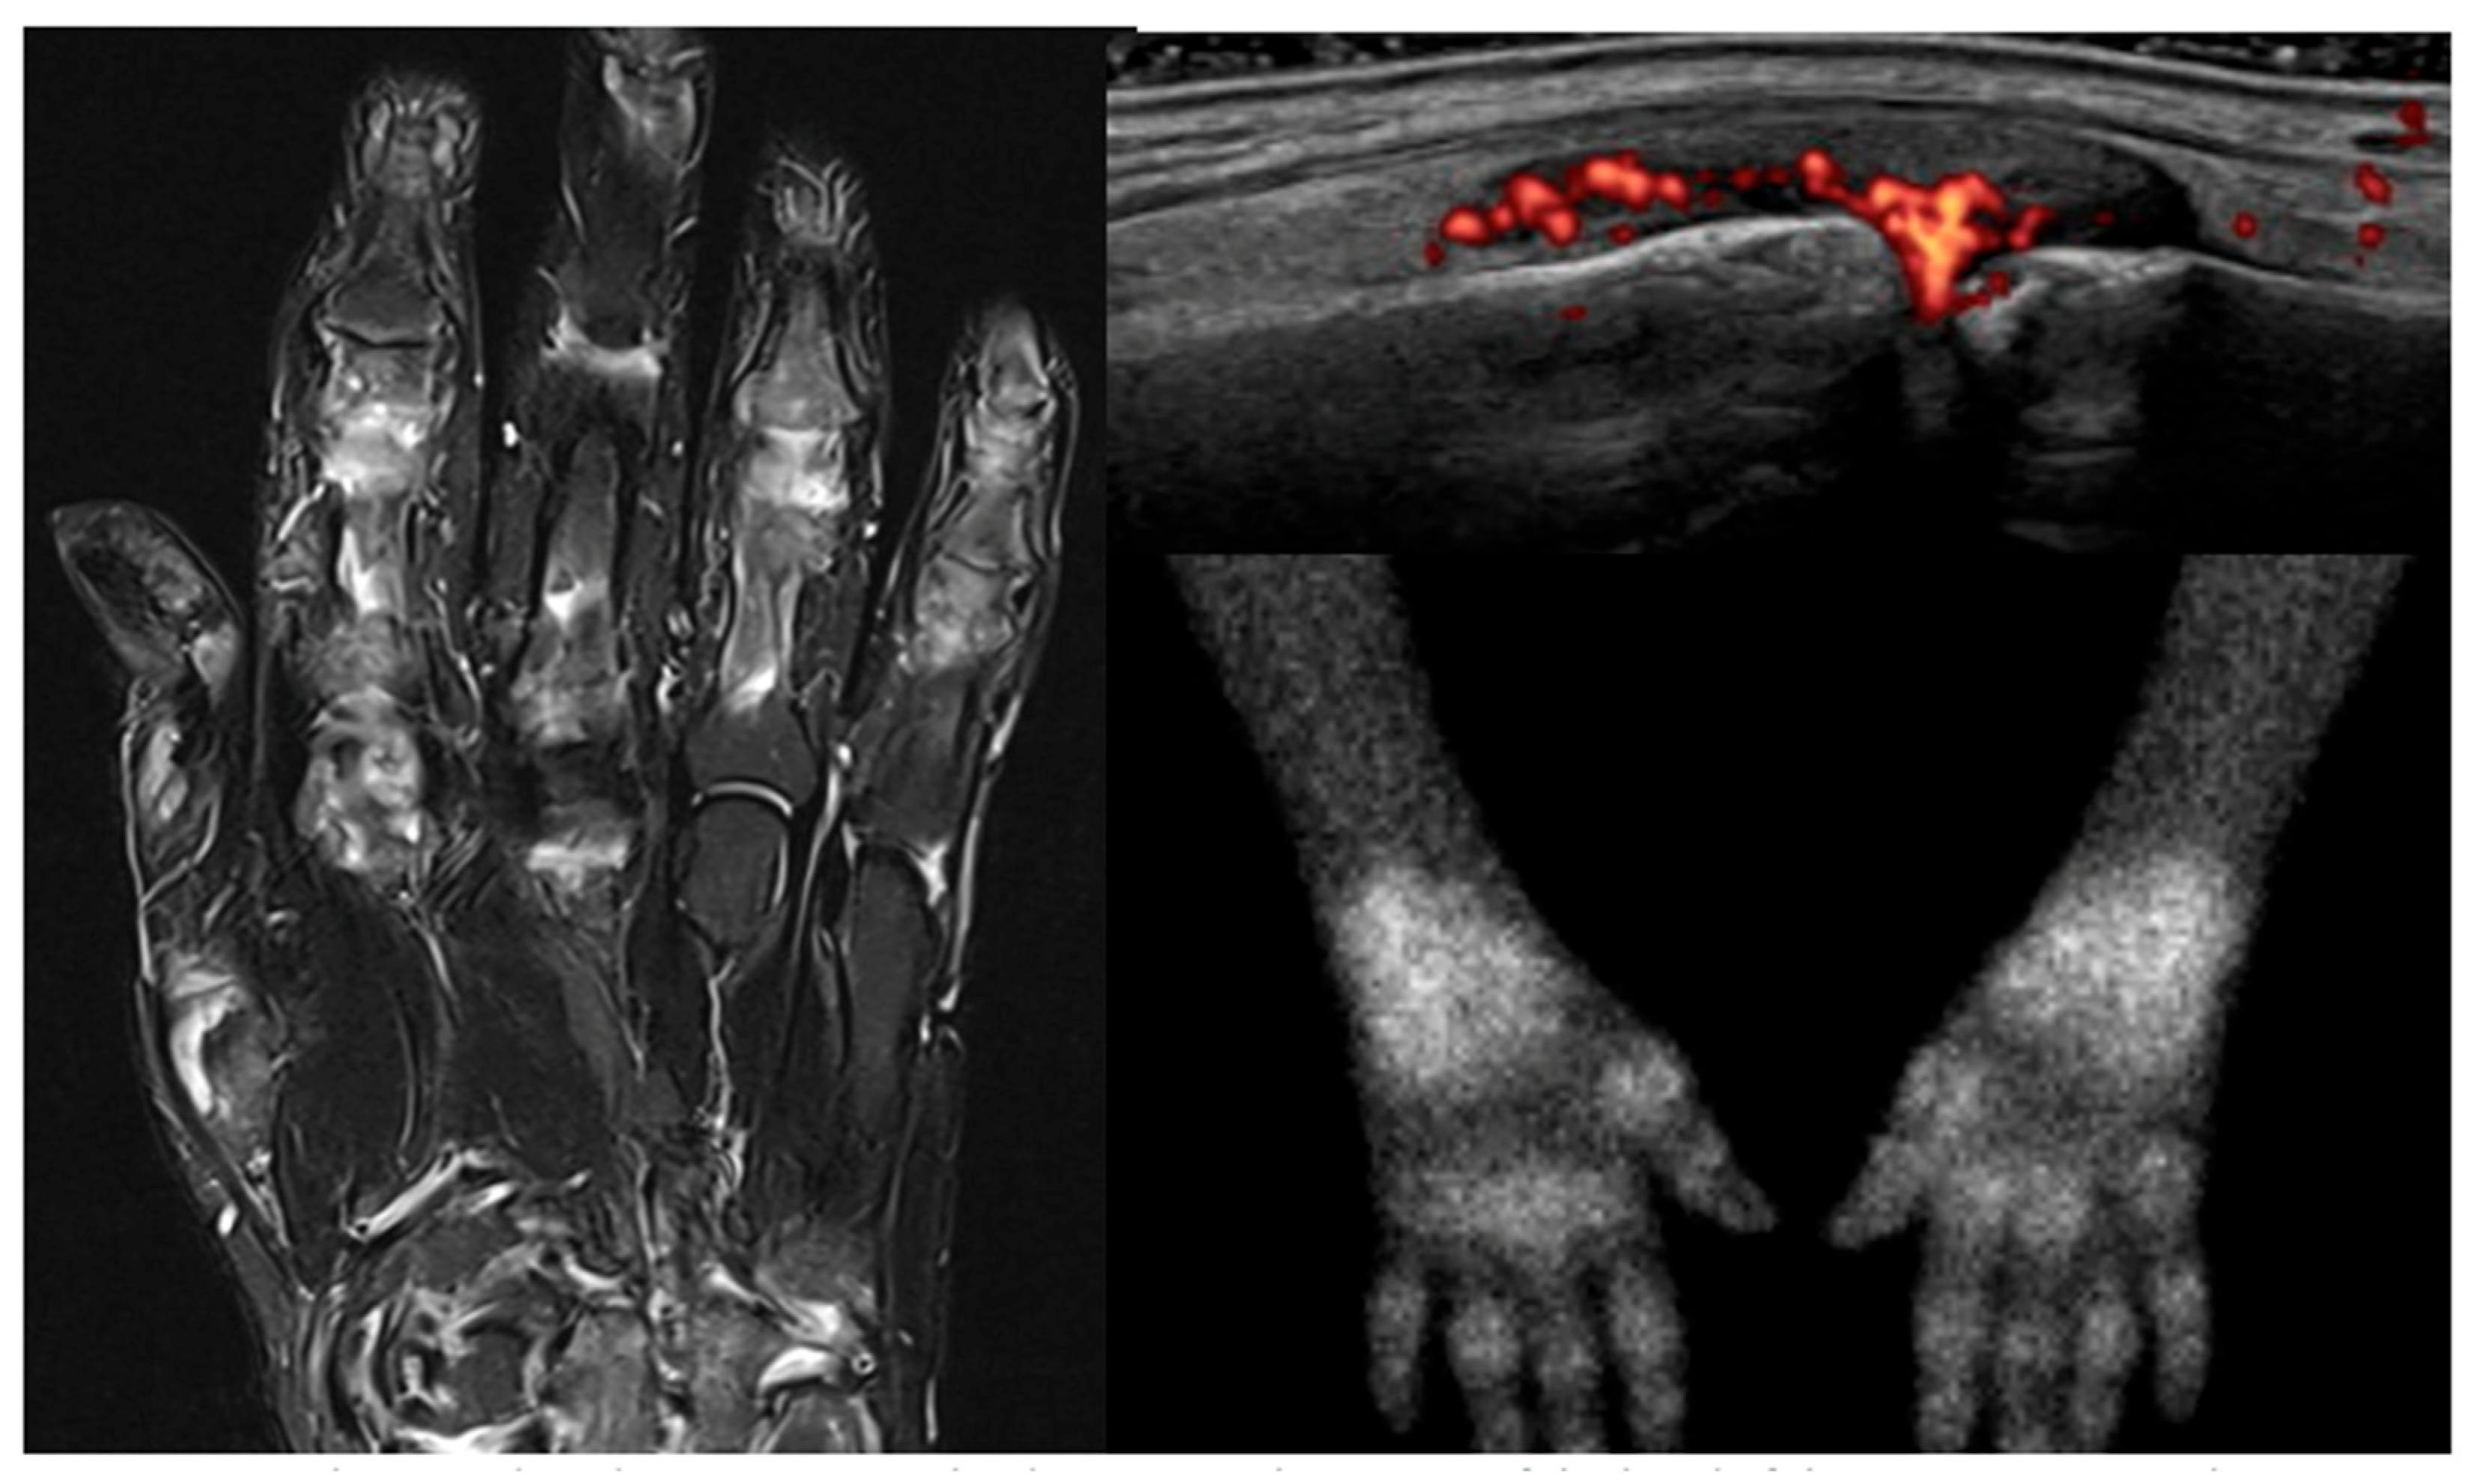

- Buchbender, C.; Ostendorf, B.; Mattes-György, K.; Miese, F.; Wittsack, H.-J.; Quentin, M.; Specker, C.; Schneider, M.; Antoch, G.; Müller, H.-W.; et al. Synovitis and bone inflammation in early rheumatoid arthritis: High-resolution multi-pinhole SPECT versus MRI. Diagn. Interv. Radiol. Ank. Turk. 2013, 19, 20–24. [Google Scholar] [CrossRef]

- Buchbender, C.; Sewerin, P.; Mattes-György, K.; Miese, F.; Wittsack, H.-J.; Specker, C.; Antoch, G.; Müller, H.-W.; Schneider, M.; Scherer, A.; et al. Utility of combined high-resolution bone SPECT and MRI for the identification of rheumatoid arthritis patients with high-risk for erosive progression. Eur. J. Radiol. 2013, 82, 374–379. [Google Scholar] [CrossRef]

- Miese, F.; Scherer, A.; Ostendorf, B.; Heinzel, A.; Lanzman, R.S.; Kröpil, P.; Blondin, D.; Hautzel, H.; Wittsack, H.-J.; Schneider, M.; et al. Hybrid 18F-FDG PET-MRI of the hand in rheumatoid arthritis: Initial results. Clin. Rheumatol. 2011, 30, 1247–1250. [Google Scholar] [CrossRef]